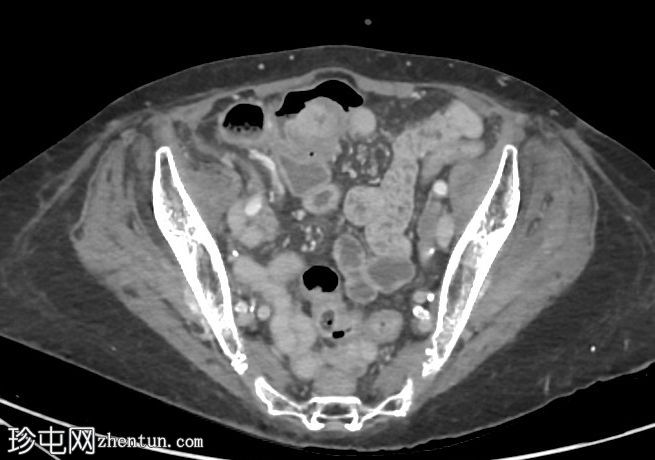

轴向C+门静脉期

阑尾盲肠极-基底部明显增厚,强化明显。阑尾中段1/3直径扩张至12毫米,远端1/3增厚。阑尾尖端周围有微小组织性液体积聚。阑尾周围无明显脂肪条带。